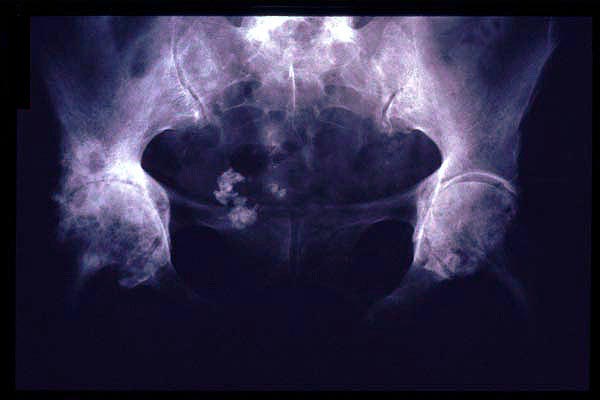

E de Paget